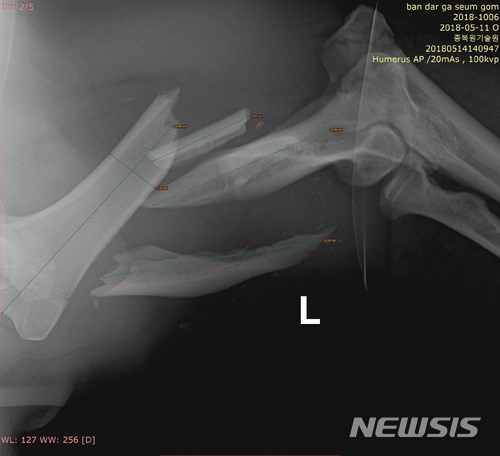

KM53은 지난 11일 치료를 받기 위해 포획됐으며 17일 오후 1시부터 12시간에 걸쳐 왼쪽 앞다리 어깨부터 팔꿈치 사이 복합골절 부위 수술을 받았다.

수술은 국립공원관리공단 종복원기술원 야생동물의료센터 정동혁 센터장과 전남대 수의대 강성수 교수팀이 함께 전남 구례군 종복원기술원 야생동물의료센터에서 복합골절 부위를 고정 장치로 접합하는 방식으로 진행됐다.

【세종=뉴시스】교통사고를 당한 반달가슴곰 KM53 복합골절 부위를 엑스레이로 촬영한 모습. 2018.05.18.(사진 = 국립공원관리공단 제공)[email protected]